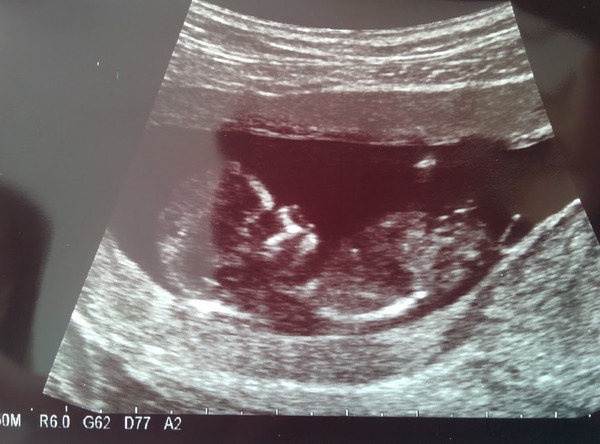

had my scan today and all well! here's my pic! baby was very wriggly, took ages to get photos/measurements. I didn't mind though as meant I got to watch baby bouncing around and kicking and moving arms. amazing!

For some reason I'm convinced I'm having a boy this time. Keep finding myself referring to baby as 'he'. I'm not under any illusions that I somehow know so I guess I have a 50/50 chance of being right! will know in 8 weeks when I have my next scan Smile

Oh marmite congratulations that's such a beautiful picture!

Congrats marmite! Gorgeous photo :-)

congrats marmite lovely pic :)

Great pic marmite! Good luck at your scan lilmiss!

Lovely pic, marmite!

Oh marmite what a lovely picture, congratulations :) I'm shite at this but I do think your baby looks like a boy.